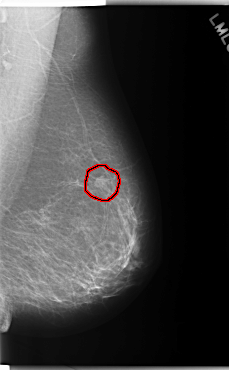

C_0187_1.RIGHT_MLO

FILE: C_0187_1.LEFT_MLO.OVERLAY

TOTAL_ABNORMALITIES 1

ABNORMALITY 1

LESION_TYPE MASS SHAPE OVAL MARGINS SPICULATED

ASSESSMENT 5

SUBTLETY 5

PATHOLOGY MALIGNANT

TOTAL_OUTLINES 1

BOUNDARY